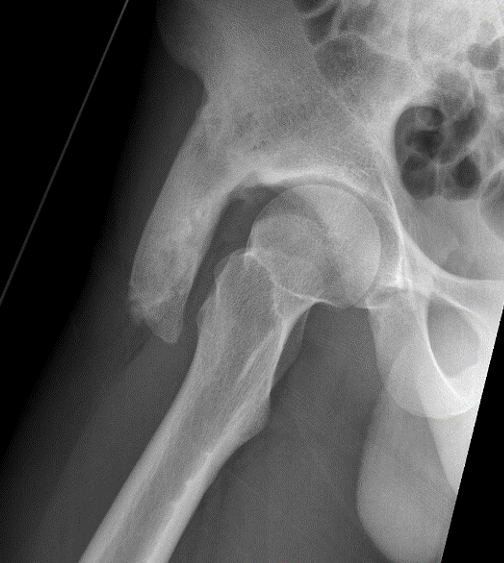

ASIS Avulsion

Attachments

Sartorius & Tensor fascia lata

Imaging

ASIS displaced 1ASIS displaced 2